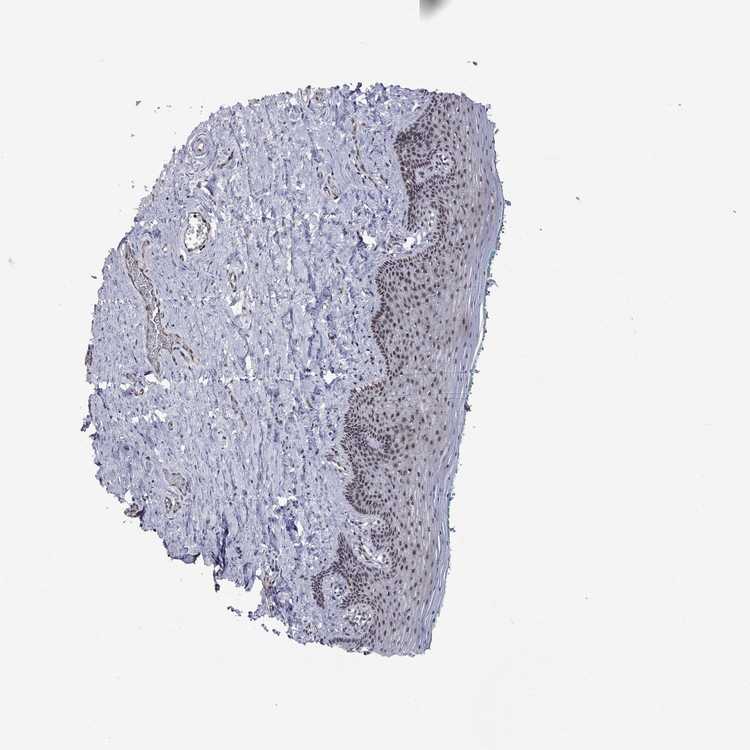

VAGINA - Antibody stainingi

Antibody staining in the annotated cell types in the current human tissue is reported as not detected, low, medium, or high, based on conventional immunohistochemistry profiling in selected tissues. This score is based on the combination of the staining intensity and fraction of stained cells.

Each image is clickable and will lead to virtual microscopy that enables deeper exploration of all samples and also displays staining intensity scores, fraction scores and subcellular localization as well as patient and tissue information for each sample.

Antibody HPA074990

Squamous epithelial cells High